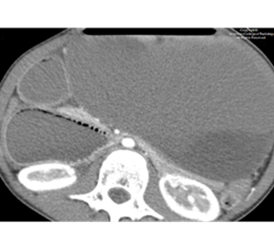

We selected this case because of its unique presentation and associated findings. The patient’s medical managing team was surprised when we communicated to them the finding of suspected gastric outlet obstruction on abdominal radiograph and recommended placement of an enteric tube with order for immediate cross-sectional imaging. They told us that the working diagnosis was constipation and were planning to treat it conservatively with enema. Follow-up computed tomography (CT) confirmed the upper gastrointestinal (GI) obstruction and revealed the underlying cause to be superior mesenteric artery (SMA) syndrome. The team was then able to elicit a history of significant rapid weight loss from the mother.

We were excited when our Attending, Dr. Hammill, agreed with our diagnosis. However, we were confused with the liver and splenic ischemic foci apparent on CT as this is not a phenomenon ever described to be associated with SMA syndrome. Dr. Hammill directed our attention to the compression of the retroperitoneal vascular structures including branches of the celiac artery by the markedly distended stomach.

It was thrilling to see on follow-up imaging that the ischemic foci on the liver and spleen resolved after gastric decompression. It was also comforting that the patient could achieve relief with conservative management of refeeding and weight gain.